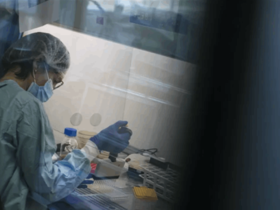

وأجرى الأطباء اختبارات كشفت عن إصابته بداء البريميات، وهي بكتيريا موجودة في بول الفئران، ووجدوا أيضًا أن لديه علامات تحذيرية من فشل متعدد الأعضاء والإنتان.

وتم إعطاؤه المضادات الحيوية، وبعد بضعة أيام تعافى بدرجة كافية للعودة إلى المنزل.